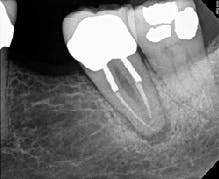

Figure 2 demonstrates a case with failing endodontic therapy. The mesial canals show inadequate obturation, and a periradicular radiolucent area is apparent. The tooth was retreated, and figure 3 shows the one-year follow-up. Note the resolution of the radiolucency. This case demonstrates the concept of removing the etiology of the bacteria with nonsurgical treatment.